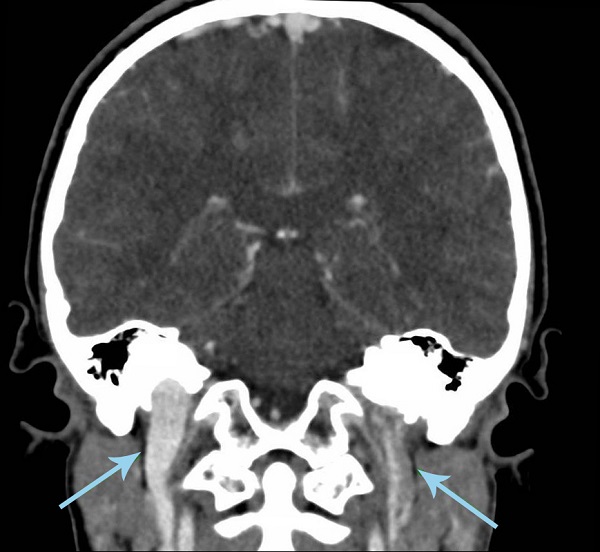

Se realiza TC craneocervical con contraste, objetivándose otomastoiditis complicada con trombosis de senos venosos cerebrales (seno sigmoide izquierdo, seno recto y ambos senos transversos), además de absceso en espacio cervical posterior izquierdo de aproximadamente 27 x 10 x 16 mm. Se informa de adecuada permeabilización de vena yugular interna izquierda.